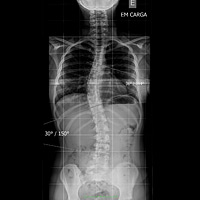

Exames

Raios X

O que é o exame?

O sistema de Raio-X Digital apresenta uma melhor qualidade e precisão da imagem gerada por raio-X principalmente mais saúde ao paciente devido a menor exposição a radiação ionizante.

Os problemas comuns na manipulação e processamento de películas convencionais são minimizados com o sistema de Raio-X Digital, reduzindo desta forma o tempo de realização dos exames e eventuais repetições na aquisição de imagens pois, o sistema digital permite ajustes na imagem captada contribuindo também para uma menor exposição do paciente ao raio-X. O sistema de Raio-X Digital permite ainda o arquivamento de exames possibilitando o estudo comparativo entre exames anteriores e actuais, auxiliando o Médico na definição e no acompanhamento de quadros clínicos.

Como é feito?

O paciente posiciona-se em frente ou sobre o aparelho de raio-x acompanhado da orientação de um técnico. É emitido raio-x na região a ser estudada e ao mesmo tempo os raio-x são captados em uma placa especial, que será processada digitalmente formando a imagem da área de estudo. Esta imagem poderá ser gravada em cd-rom ou impressa em película. No sistema digital a imagem gerada é armazenada em cd-rom, que através de software específico pode-se obter a visualização, mensuração, ampliação e manipulação desta imagem auxiliando o Médico a obter maior precisão em seu diagnóstico e mais comodidade ao paciente em seu transporte devido ao tamanho do cd-rom em relação ao filme convencional.

Recomendações ao paciente

RX SIMPLES: não há preparação (Rx seios perinasais, tórax, cavum, articulações e etc..), salvo em casos específicos em que o médico solicita no pedido médico a realização de preparação para a execução do exame.